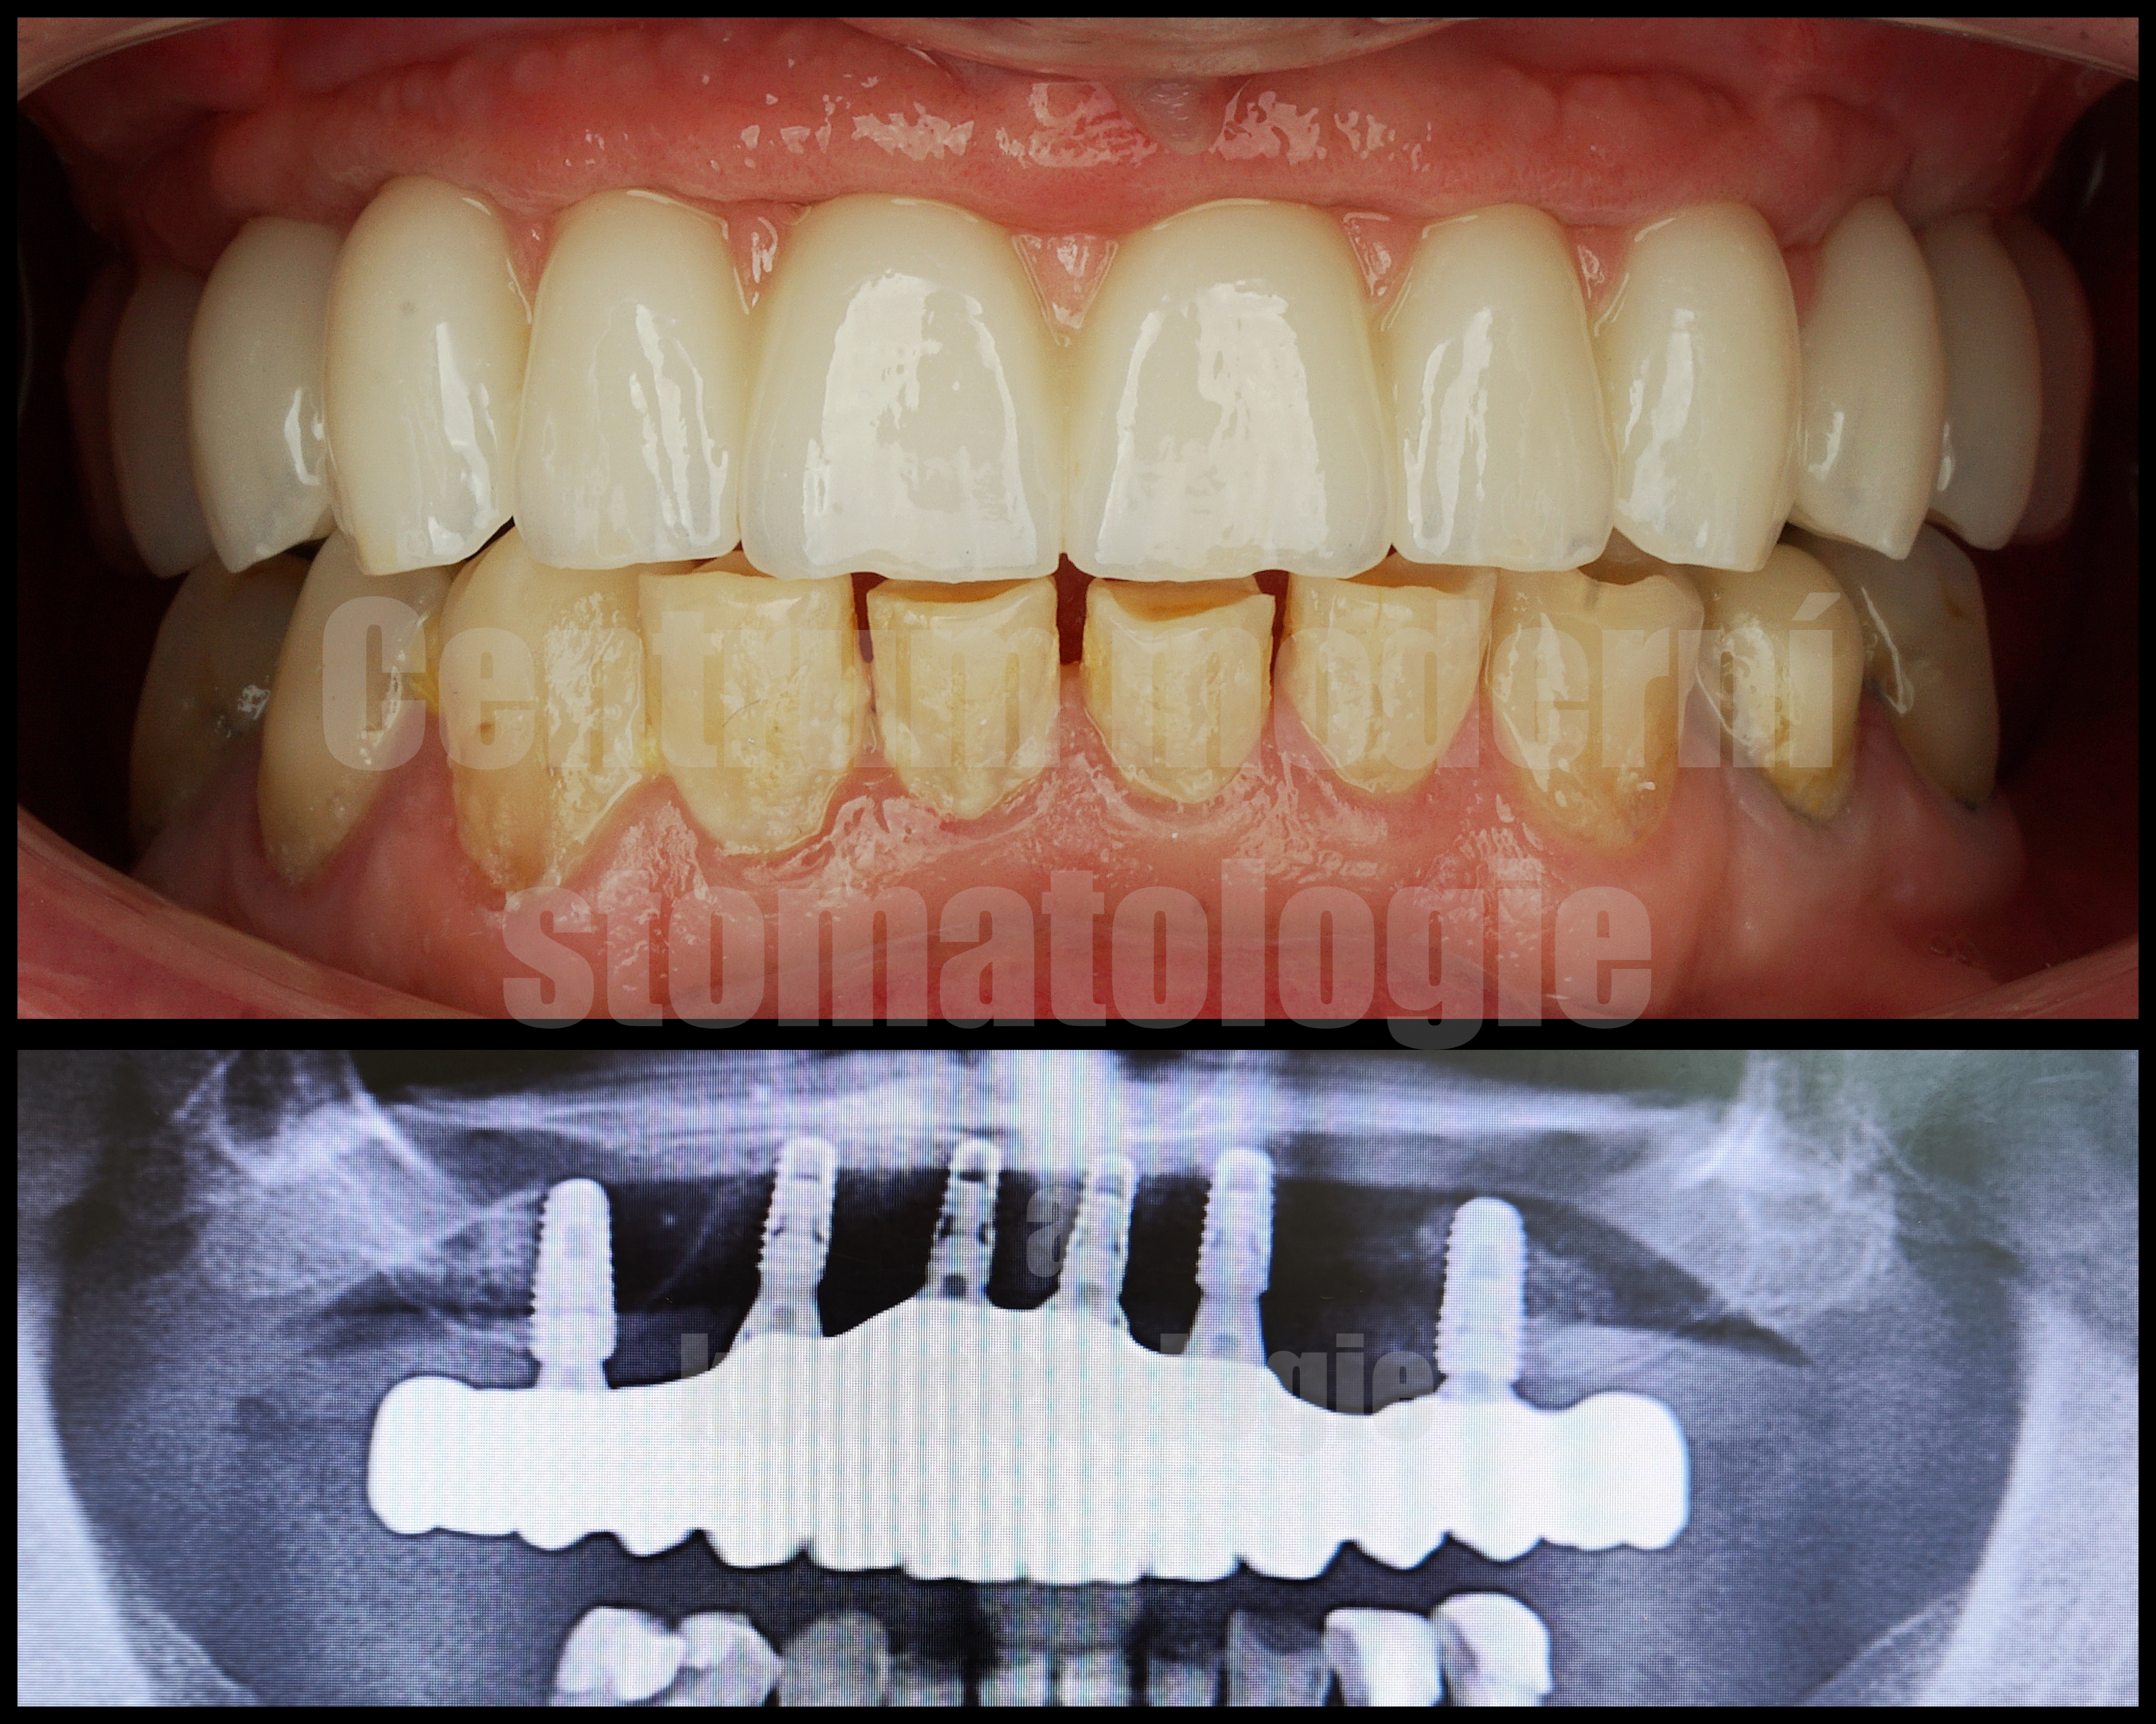

All-on-6 je moderní způsob náhrady celého zubního oblouku pomocí šesti implantátů, na kterých je upevněna fixní protetická práce.

Léčba All-on-6 začíná vstupní konzultací, při které zhodnotíme stav chrupu, dásní a kostní tkáně. Součástí plánování je klinické vyšetření a zobrazovací diagnostika.

Pokud jsou přítomny zuby, které již nelze dlouhodobě zachovat, může být součástí léčby jejich odstranění. Následně je podle léčebného plánu zavedeno šest implantátů, které slouží jako opora budoucí fixní náhrady.

Po implantaci následuje hojení. Za vhodných podmínek je v některých případech možné provést dočasné zatížení protetickou náhradou v krátkém čase po zákroku. Definitivní práce se zhotovuje po stabilizaci a vhojení implantátů.

U některých pacientů po ztrátě zubů dochází k úbytku kostní tkáně. Pokud není kostních podmínek dostatek, může být součástí léčby augmentace kosti nebo jiný chirurgický postup podle konkrétního nálezu.